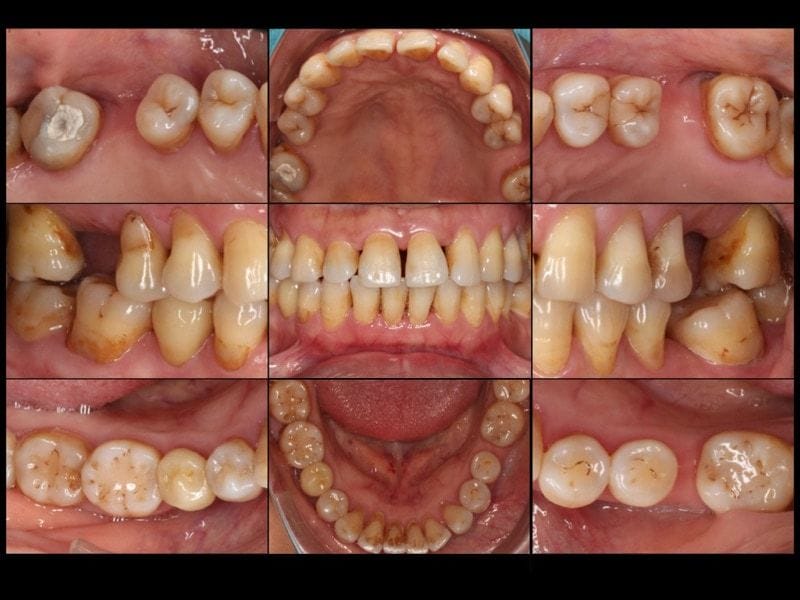

圖示:被診斷為第三期全口嚴重牙周病的各角度牙齒近照

圖示:被診斷為第三期全口嚴重牙周病的各角度口腔X光照